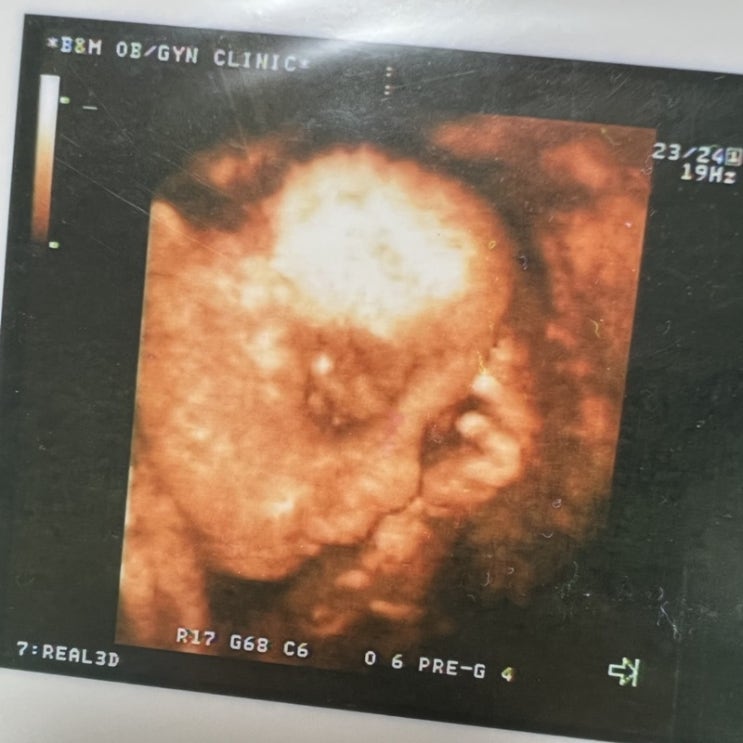

결혼 5년 차, 저희 부부는 간절히 아이를 원했지만 좀처럼 소식이 없어 걱정이 이만저만이 아니었어요. 혹...

저는 둘째 준비를 하고 있어요. 결혼을 하면서 남편과 얘기한 자녀 계획은 둘이었어요. 혼자는 외로울 것 ...